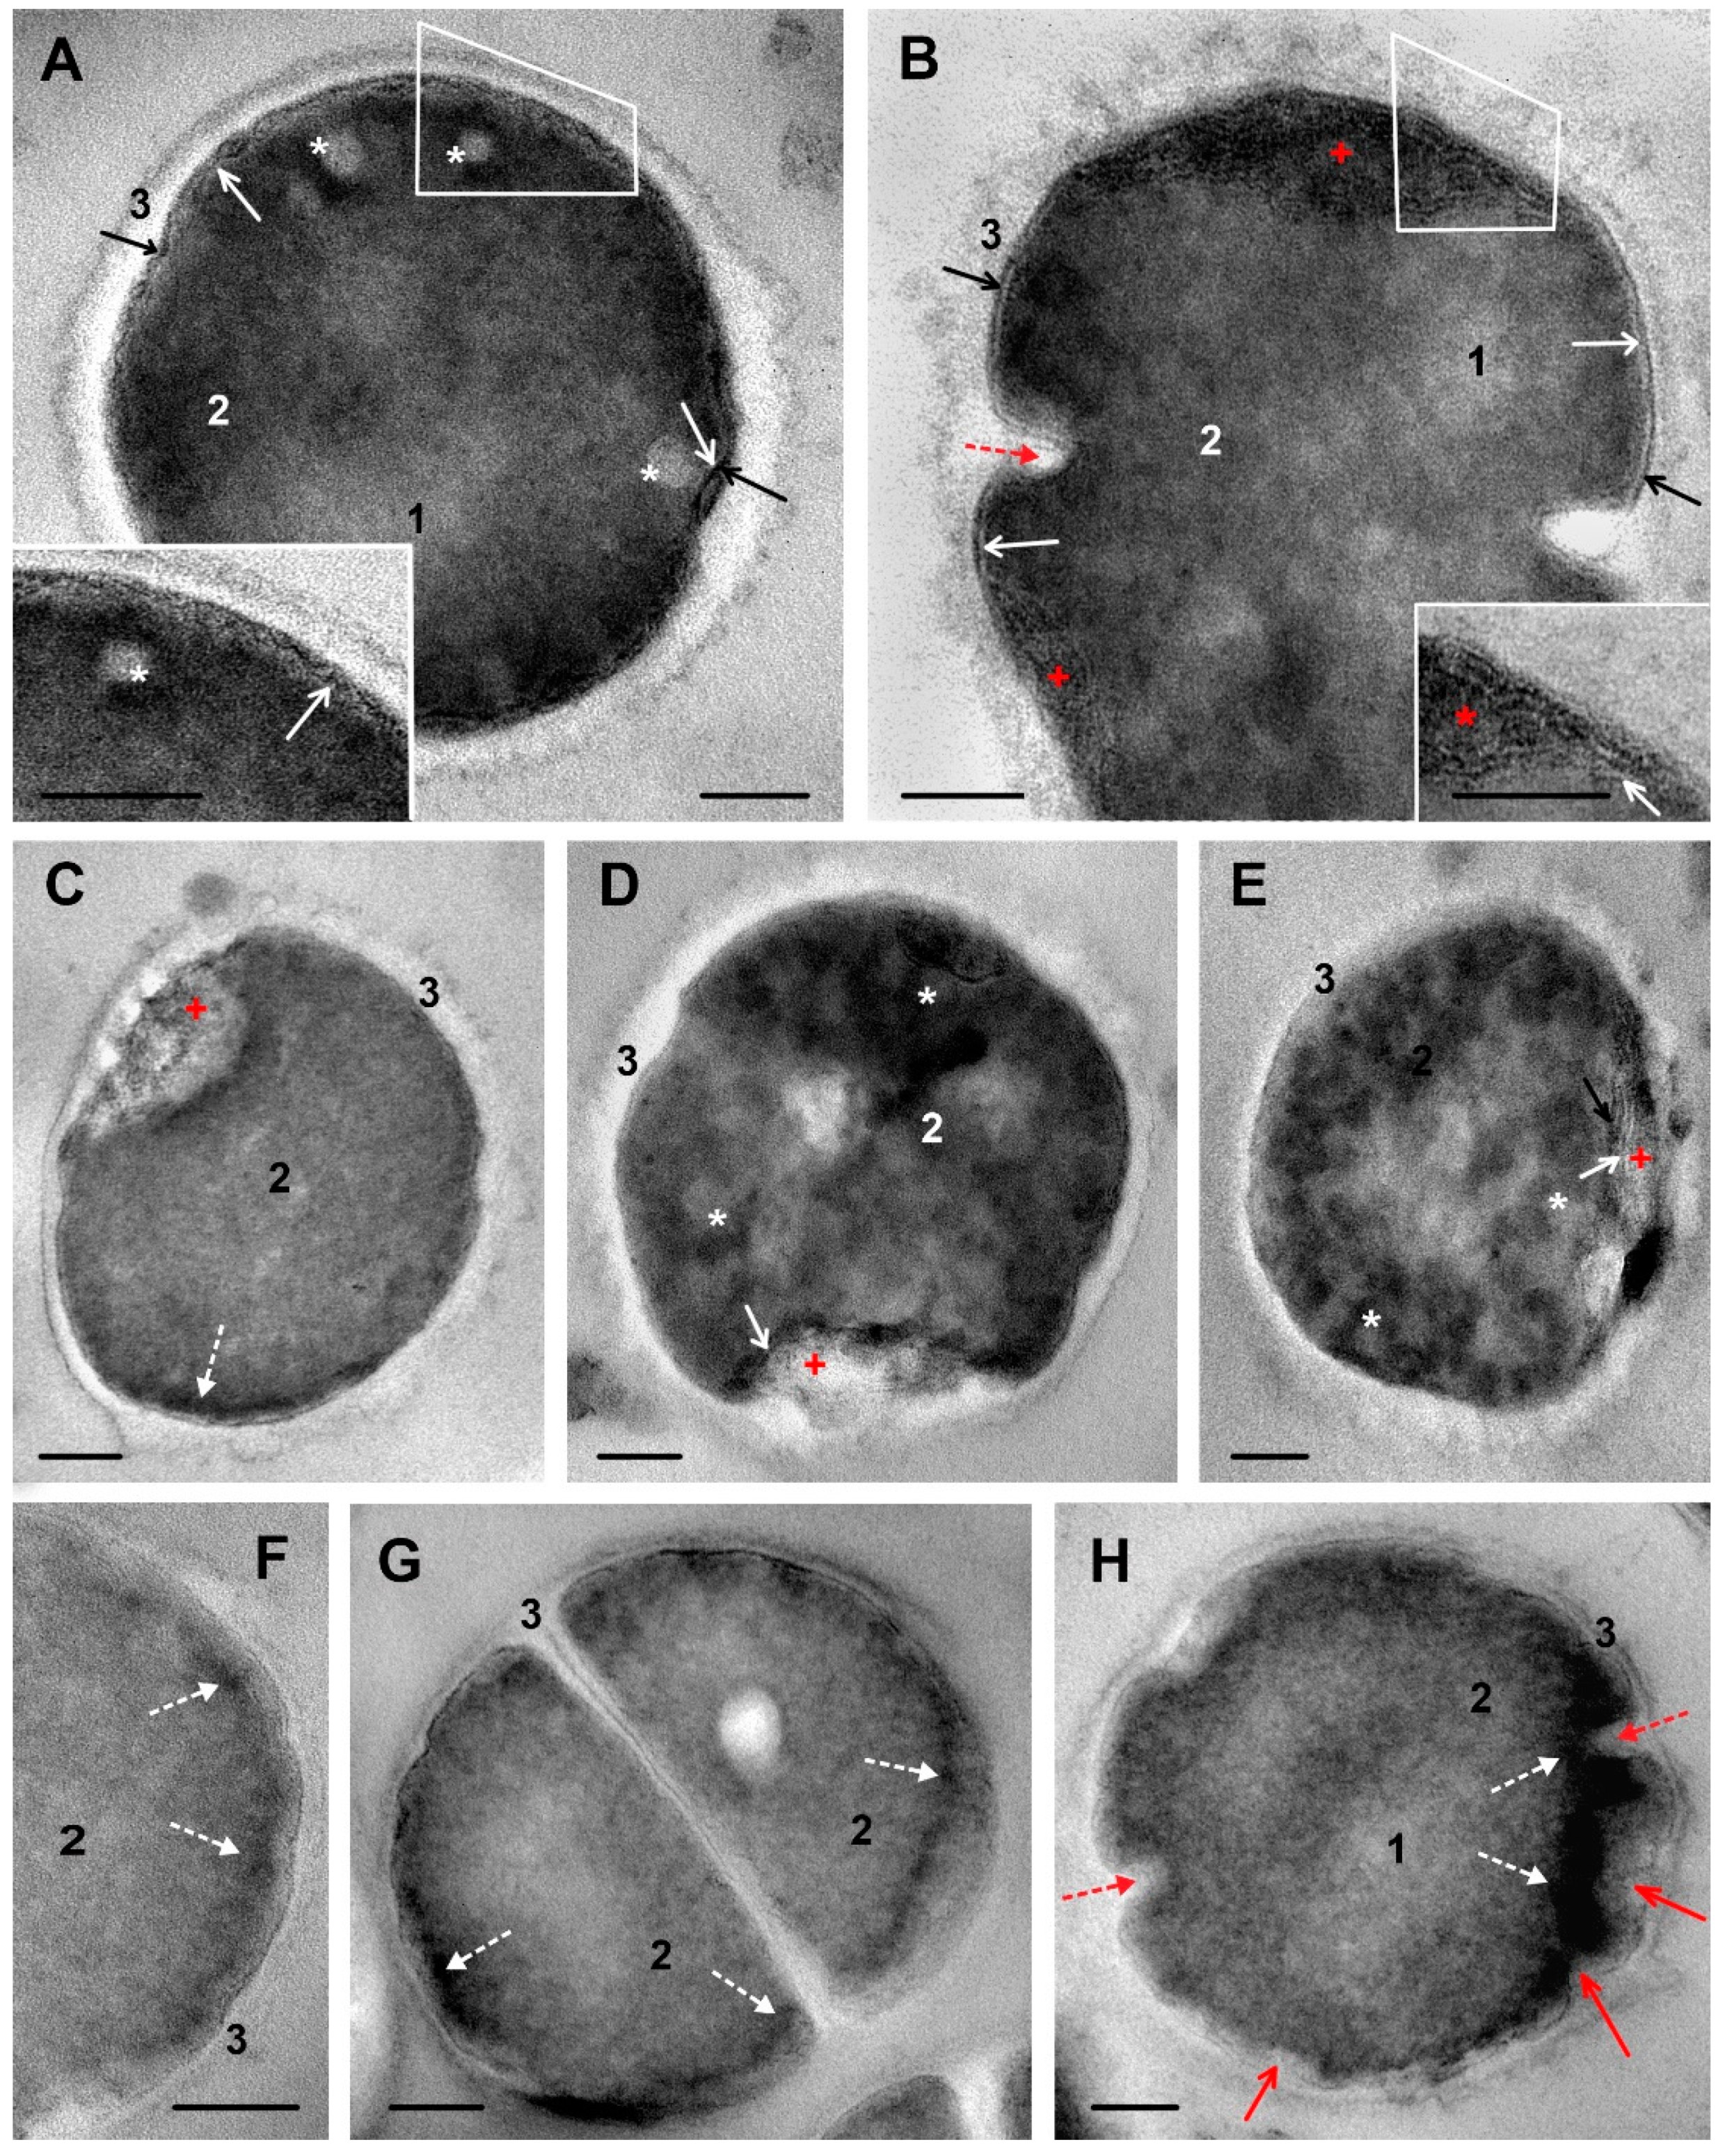

Figure 4. Changes in ultrastructure of S. aureus cells incubated with hybrid DL5Cip6. (A)—prominent folding of cell membrane and damage of intermediate layer; insert: enlarged area inside a contour. (B)—a “bowl”-like structures composed of cell membrane folds, which enclose electron-dense material; insert: enlarged area inside a contour. Note alteration of cell wall structure. (CE)—variants of “bowl” shape. (C)—a cell with minor structural disturbances, cell wall covering a “bowl” contains strands of medium electron density. (D,E)—cells with clumpy cytoplasm and altered cell wall; “bowl” areas contain membrane fragments and electron-dense material. (FH)—the appearance and accumulation of electron-dense material in S. aureus cells. (F)—small clumps; (G)—electron-dense material in the cytoplasm along cell periphery; (H)—“staining” of cytoplasm by electron-dense material. 1—blurred area of nucleoid; 2—cytoplasm; 3—cell wall; white arrows show cell membrane; black arrows—intermediate layer; asterisks—spherical structures in cytoplasm; red arrow—folds of cell membrane and intermediate layer; broken red arrow—septum formation; red cross—“bowl”-like structure; broken white arrows—electron-dense material; red arrows—deformation of cytoplasm. TEM, ultrathin sections. The length of the scale bars corresponds to 100 nm.

Figure 4 shows representative illustrations of ultrastructural changes in S. aureus cells incubated with DL5Cip6. Figure 4A–E demonstrates changes that can be attributed to the ciprofloxacin effect, and Figure 4F–H those that can be attributed to the DL412 effect.

The impact of DL5Cip6 on S. aureus led to loosening of the cell wall and loss of its outer border clarity. Changes in the wall developed gradually, the images show areas of a smooth wall and areas of pronounced alteration (Figure 4). At the same time, cell wall thickening, which was a feature of DL412 effect, was absent.

The cell membrane of S. aureus was affected by DL5Cip6, and these changes were similar to those observed in bacteria treated with ciprofloxacin, but were of a higher degree. The cell membrane, visualized by the electron-transparent layer, lost its structure and, together with the adjacent intermediate layer, formed small folds (Figure 4A), like those in ciprofloxacin treated cells. Then, folds of the cell membrane increased in size and formed structures resembling a “bowl”, which contained an electron-dense material surrounded by a membrane (Figure 4B). We observed different varieties of “bowl”-like structures, containing structureless material, probably destroyed cytoplasm. All “bowl”-like structures were clearly separated from cytoplasm (Figure 4C–E). In the image of a cell with minor structural disturbances, strands of a substance of medium electron density are visible in the cell wall covering the “bowl” (Figure 4C). Figure 4D,E show cells with clumpy cytoplasm and altered cell wall, fragments of membranes and electron-dense material are visible in the bowl area.

The loss of structure by the S. aureus cytoplasm upon ciprofloxacin treatment began with the formation of low electron density spheres at the interface between the cytoplasm and the cell membrane (Figure 2D–F). The same structures were observed in S. aureus cells exposed to DL5Cip6 (Figure 4A; several low electron density spheres, and Figure 4D,E; blurred spheres of low electron density).

The clearest manifestation of the effect of DL412 in the composition of the DL5Cip6 molecule was the appearance and accumulation of an electron-dense material along the periphery of the cytoplasm (Figure 4F–H). Electron-dense material in S. aureus cells, when exposed to DL5Cip6, first settled down as small clumps that formed a discontinuous layer near the cell membrane (Figure 4F,G). Then, the material accumulated and, as a rule, spread into the cytoplasm, giving it a high electron density (Figure 4H). However, clearly defined electron-dense bodies, as under the action of DL412, were not formed. The cytoplasm looked “stained”; an electron-dense substance, as such, was not visible, in contrast to the effect of DL412, which indicates a different interaction of the DL5Cip6 and DL412 molecules with the cytoplasm.

Our study revealed that the action of DL5Cip6 on S. aureus combined the effects of its components, ciprofloxacin and DL412, but this combination is not a simple sum. The effect of ciprofloxacin dominated in ultrastructure changes in cells treated with DL5Cip6, although the hybrid did not suppress cell division as ciprofloxacin. In general, the degree of injury under the influence of DL5Cip6 was higher than in ciprofloxacin.